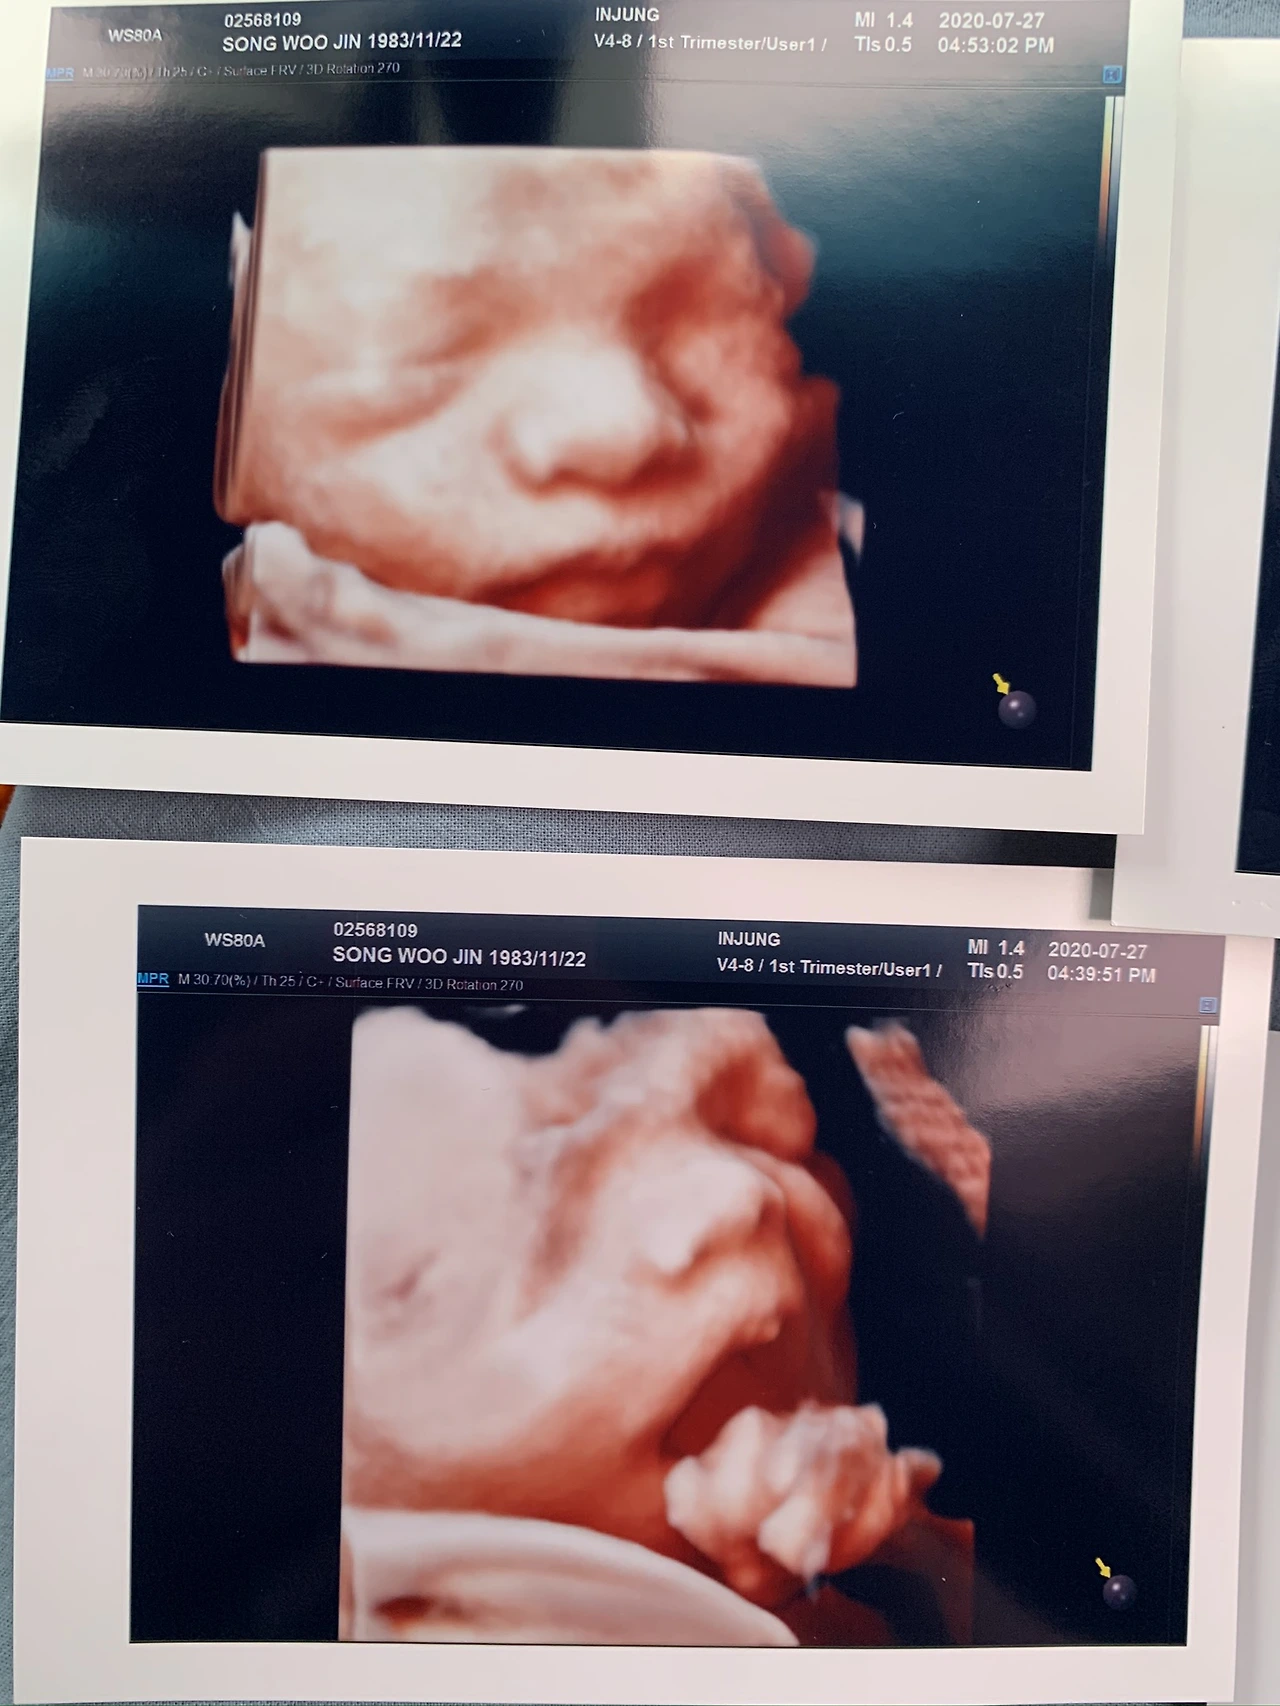

임신을 하고 네이버 블로그를 다시 시작했다. 출산을 앞두고 휴가를 길게 내기 때문에 시간 여유도 많았지만, 몸이 무거워서 다른 일을 욕심내기 어려웠기 때문이다. 2003년에 처음 시작했던 블로그는 생각보다 시간이 많이 들었다. 내 삶이 바빠지고, 내 안에서 정리해야 할 생각들이 줄고, 또 누군가에게 나의 내밀한 이야기를 털어놓기 시작하면서 블로그는 점점 멀어져갔다.

이런 버킷리스트를 과감하게 작성하다니. 역시 그 시절 나는 '육아'에 대해 아무것도 모르는 무지랭이였던 것이다. 귀로 딱지가 앉게 들었던 '뱃속에 있을 때가 행복한 것이다'라는 말은 왜 늘 실제 아이가 태어난 이후에 실감하게 되는 것인지. 남들이 다 그렇게 힘들었다고 하는 육아를 왜 나는 쉽게 갈 수 있을거라고 자만했는지

송우진님 신생아 (36).JPG

IMG_6303.JPEG